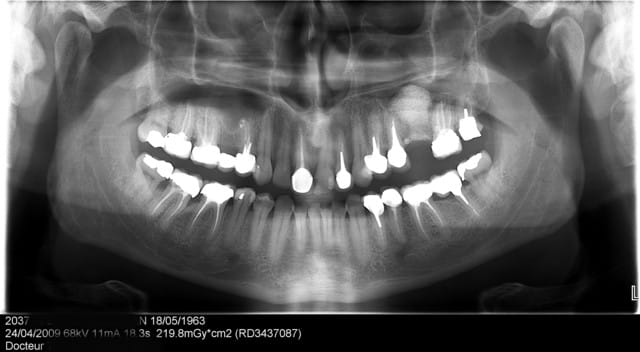

26/04/2009 à 17h06

La première fois ne fût pas agréable, parce qu'il s'agit de mon premier implant perdu!

Le deuxième dépucelage concerne mon premier SINUS LIFT.

Tu avais combien en hauteur D'os avant ton sinus lift... ?

salut dentiste 57, je suis comme toi partisan de la pose d'un implant dans ce cas là, la 15 ne me semble plus assez solide pour supporter un bridge. J'ai juste une question : sur la pano il semble y avoir une hauteur osseuse favorable, n'aurait il pas été possible de mettre un implant court ( 8,5 ou 9 mm) avec un petit punch?